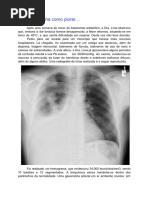

Migração do tubo para o brônquio D

• Ocorre em até 10% dos pacientes

• Anatomia favorece a migração

• O pulmão isolado entra em atelectasia, podendo

ocorrer hipoxemia em decorrência do shunt.

• Pode ocorrer barotrauma no pulmão ventilado

•  A usculta pulmonar: isoladamente, pode falhar no

diagnóstico da intubação seletiva

• Expansão dos dois hemitórax: melhor que a ausculta

• RX: confirma o diagnóstico